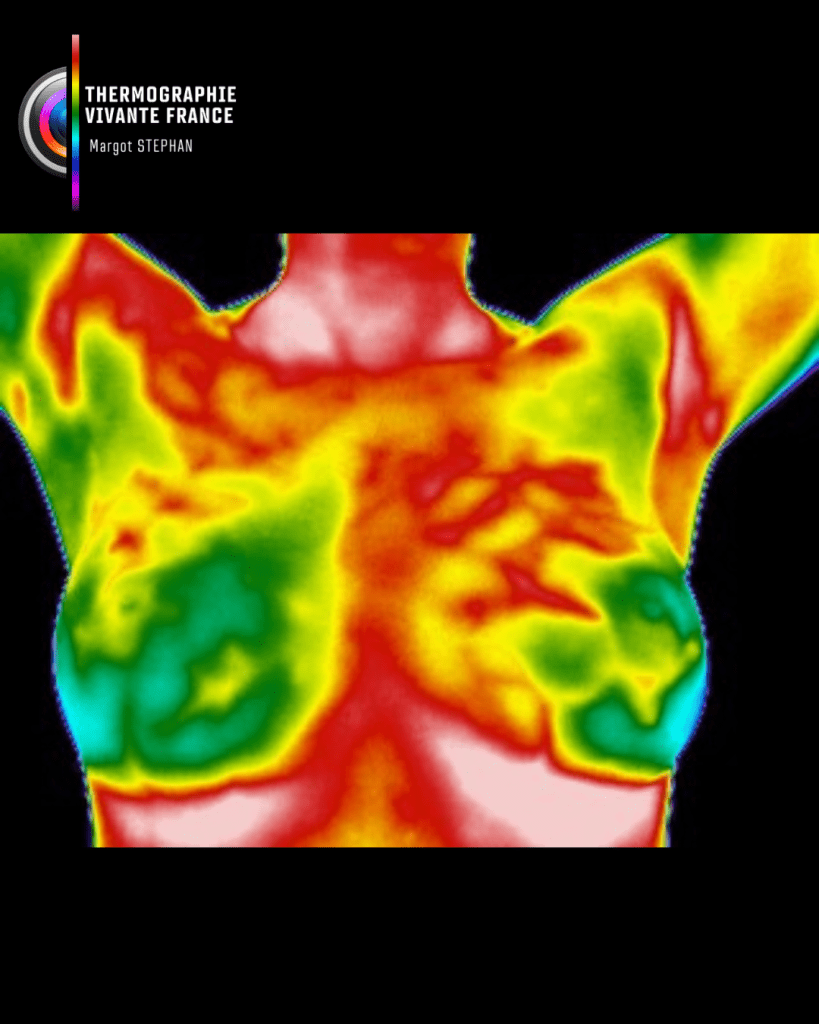

La thermographie vivante est une méthode d’imagerie fonctionnelle non invasive, sans contact, sans rayons, indolore, qui permet de visualiser la carte thermique du corps humain. Elle détecte les variations de température cutanée, révélatrices de phénomènes physiologiques internes : inflammation, surcharge fonctionnelle, tension musculaire, déséquilibres vasculaires, métaboliques ou neurologiques.

Elle révèle plutôt comment ces tissus fonctionnent en temps réel, en mesurant les émissions naturelles de chaleur générées par l’activité métabolique du corps.

La température cutanée que la caméra thermique capte n’est pas un simple reflet de la peau. Elle exprime les interactions profondes entre les systèmes vasculaire, neuromusculaire, inflammatoire et endocrinien.

Elle permet ainsi de détecter :

- Des zones de surchauffe (inflammation, surcharge fonctionnelle)

- Des zones de froid anormal (hypoactivité, trouble circulatoire, déconnexion neurovasculaire)

- Des asymétries thermiques révélant une compensation posturale ou une perturbation fonctionnelle

Un tissu qui souffre, qui s’emballe, qui ralentit ou qui compense ailleurs laisse toujours une empreinte thermique identifiable.

Sauf cas particulier (ex. thermographie mammaire), chaque premier rendez-vous commence par une cartographie corps entier. Car le corps fonctionne en interactions, pas en pièces détachées.